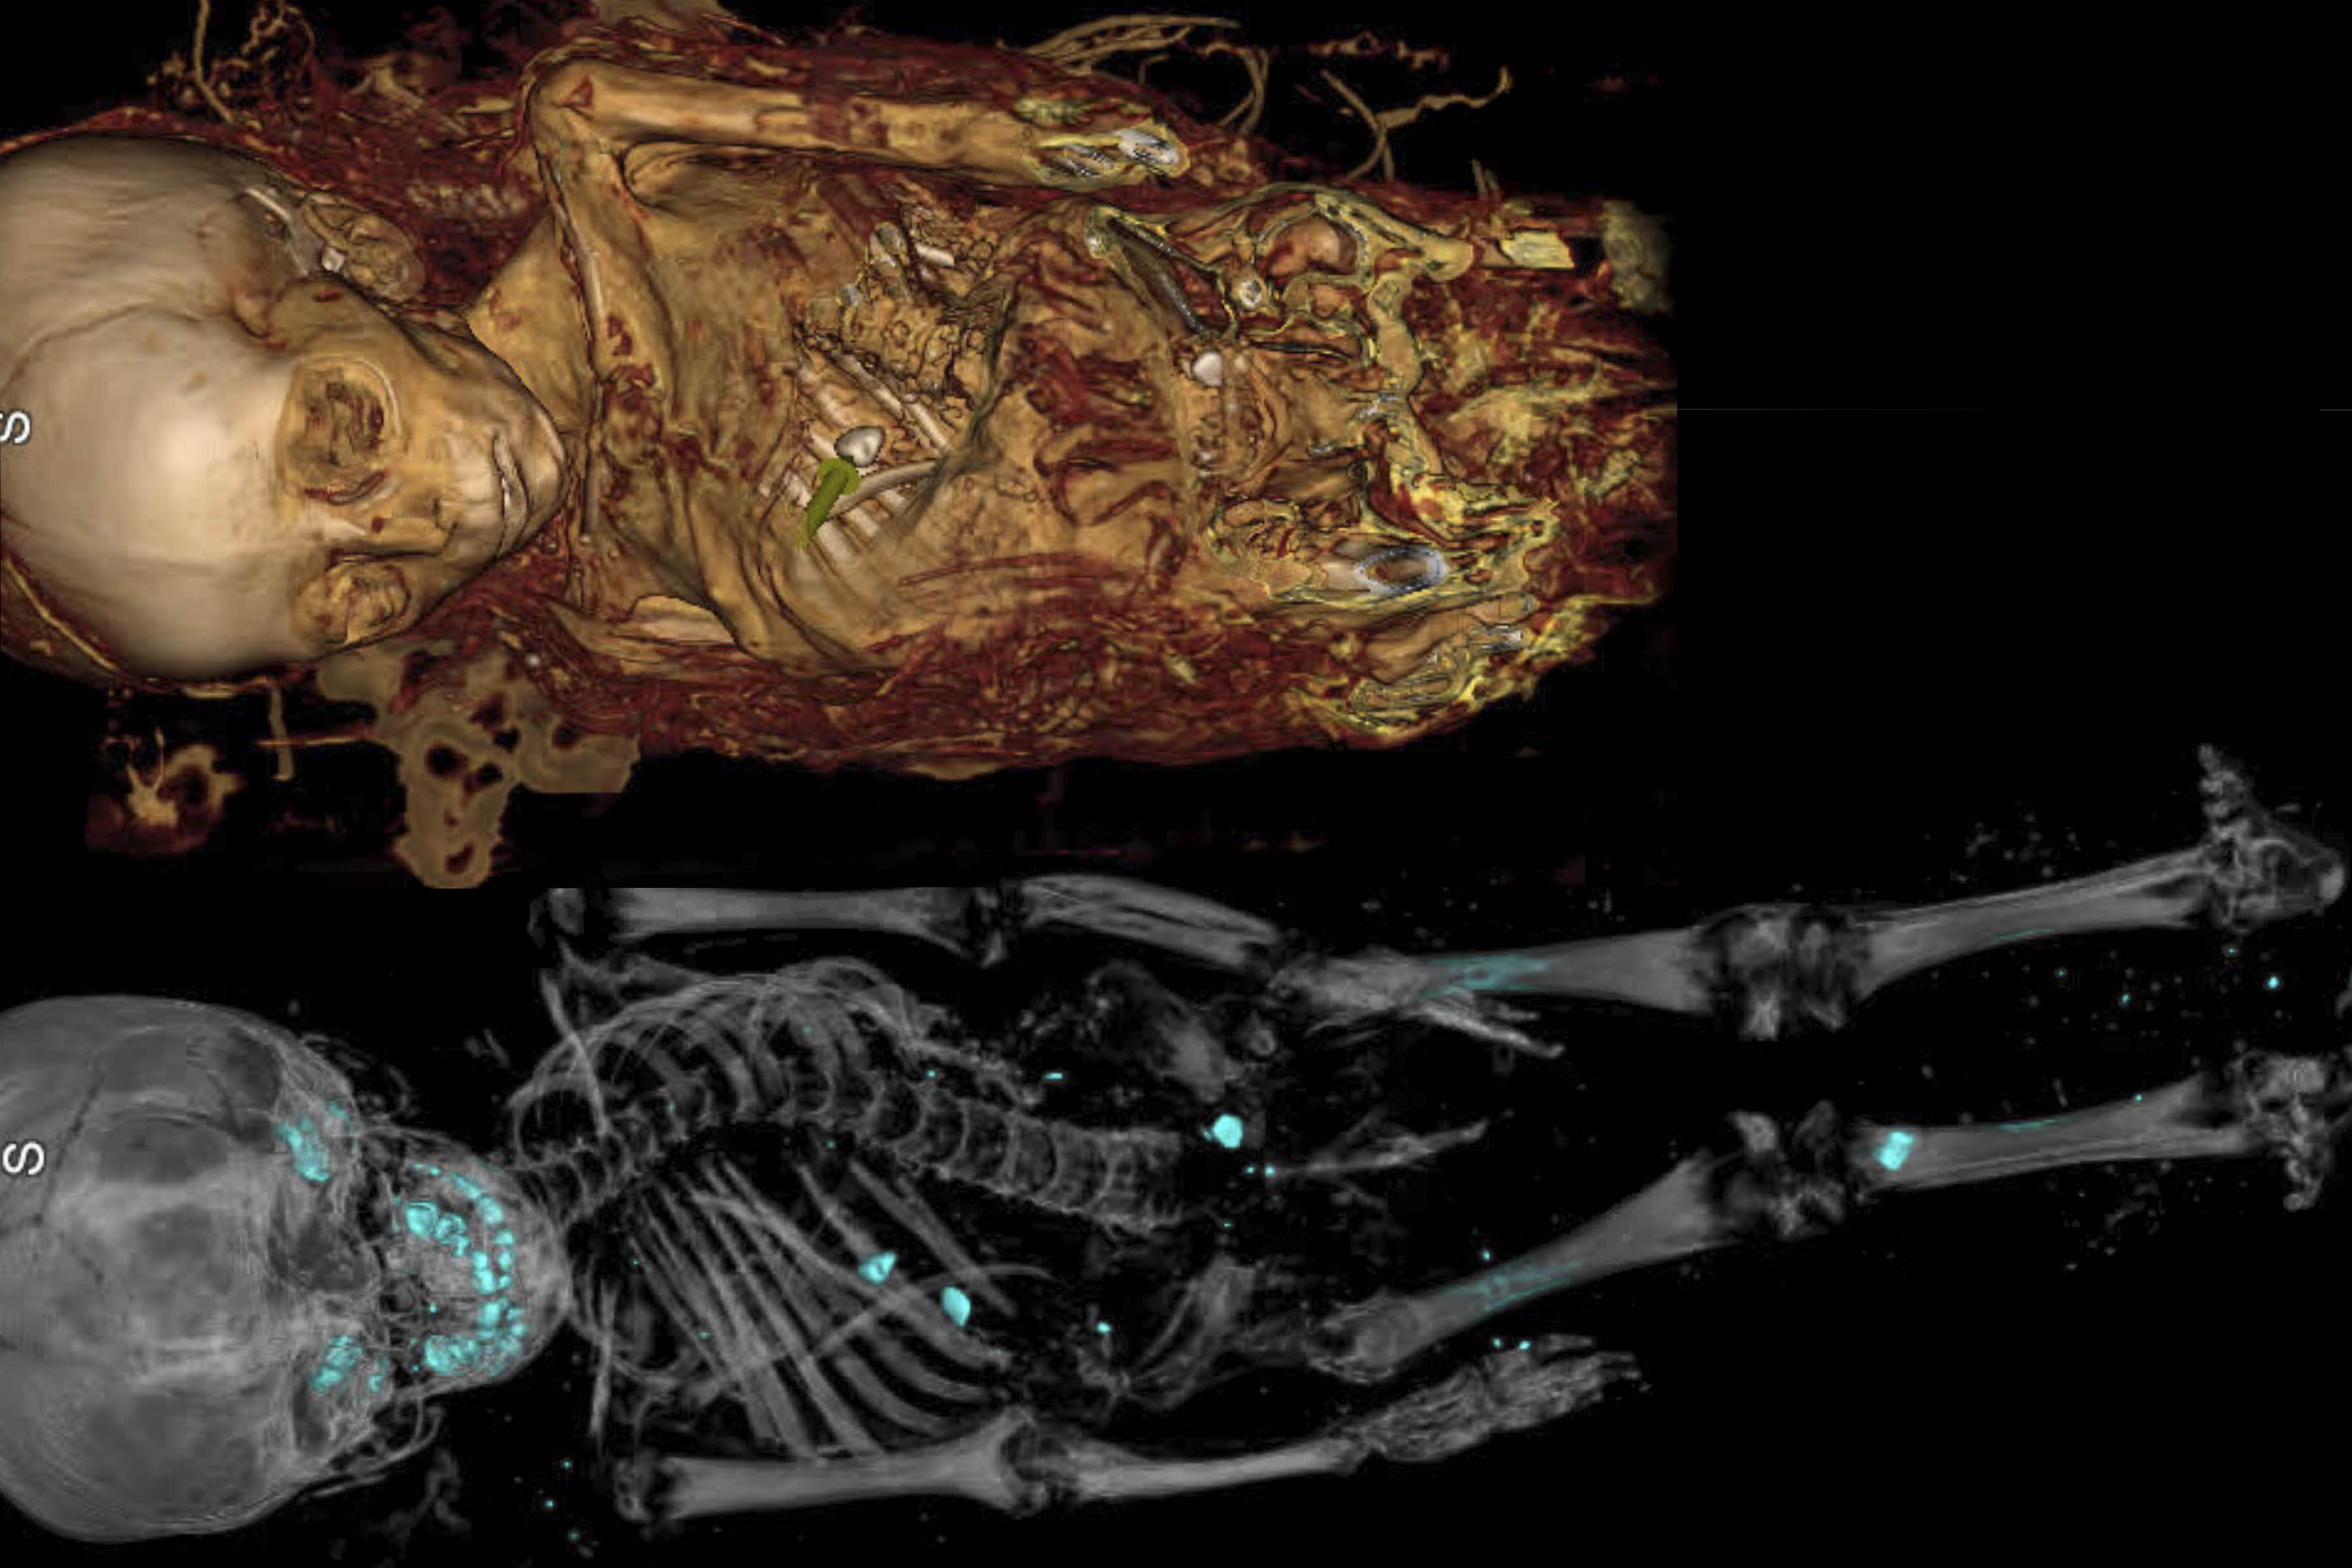

Washington University School of MedicineA baby mummy (above) and pieces of skull from two Triceratops underwent computed tomography (CT) scans at Washington University School of Medicine in St. Louis on Saturday, Sept. 16. The mummy and the skulls belong to the Saint Louis Science Center. See more scans and photos below.

The mummified remains of a 7-month-old baby boy and pieces of skull from two teenage Triceratops underwent computed tomography (CT) scans Saturday, Sept. 16, at Washington University School of Medicine in St. Louis, in hopes researchers could learn more about their ancient pasts. The project is a collaboration between the Saint Louis Science Center and the School of Medicine.

By scanning the child mummy, researchers hope to gain insight into the diet, lifestyle, habits and physiology of people living in Egypt around 2,000 years ago, when the baby was mummified. They also are looking for clues to how the baby died.

The child mummy has been part of the Science Center’s collections since 1985, when it was donated by the relatives of a man who acquired it on a trip to Egypt in the late 19th or early 20th century. Decades ago, someone cut away the wrappings around the shoulders, leaving the mummified baby’s head exposed.

A previous scan performed at the School of Medicine about 10 years ago showed four amulets, or fragments of amulets, nestled deep within the wrappings, but with the technology at that time, it was impossible to see whether they bore any patterns or symbols.

The new scan of the child mummy took only a minute, and researchers from the Science Center and the School of Medicine crowded around computer monitors to see the initial results. To everyone’s surprise, a fifth amulet – possibly a heart scarab amulet – was visible inside the chest cavity near where the heart once was. It was too early to say whether it had been placed inside the baby’s chest deliberately or had fallen into the body over the centuries. The team expects to learn more about the amulets and the skeleton as they study the images.